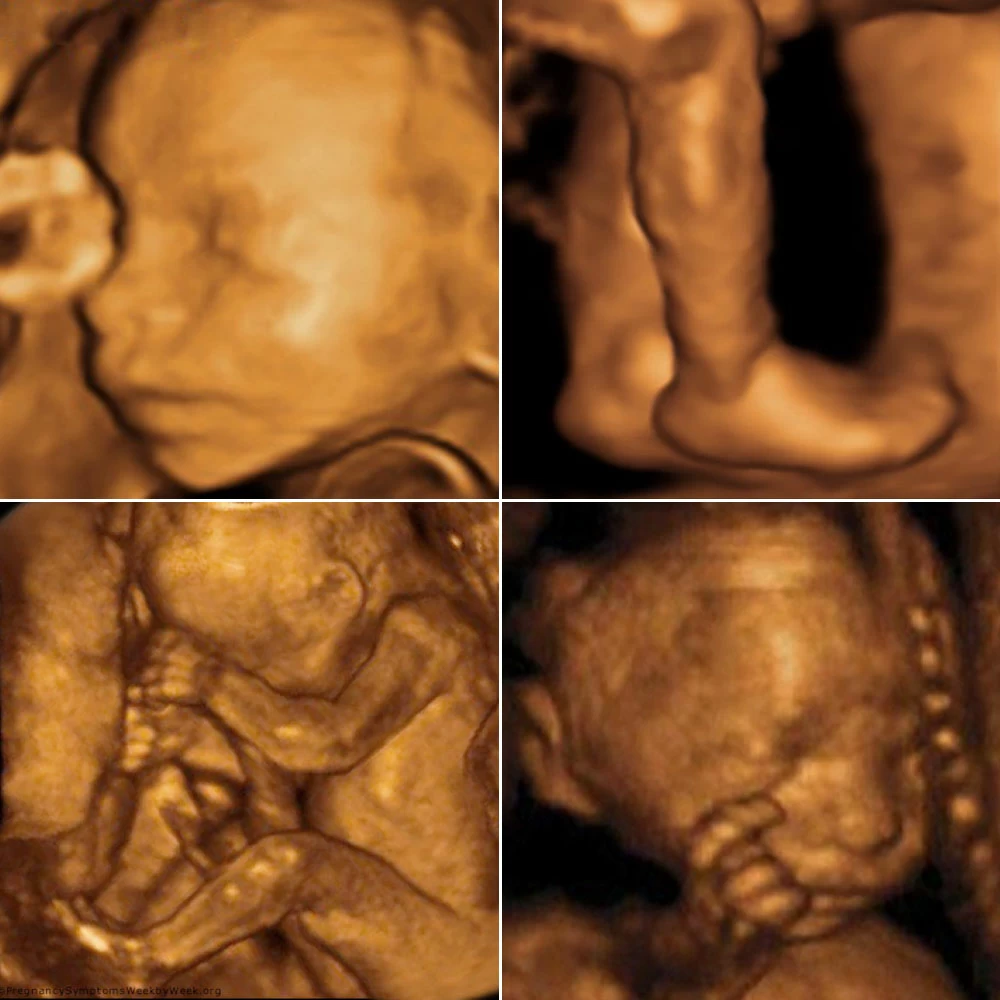

Неделя № 8

Тело эмбриона начинает выпрямляться, длина от темени до копчика составляет 15 мм в начале недели и 20-21 мм на 56 день, лицо ребенка становится привычным для человека: хорошо выражены глаза, прикрытые веками, нос, ушные раковины, заканчивается формирование губ.Отмечается интенсивный рост головы, верхних и нижних конечностей, начинается окостенение длинных костей рук и ног и черепа. Хорошо заметны пальцы. Восьмой неделей заканчивается эмбриональный период развития. Зародыш с этого времени называется плодом.

Неделя № 9

В начале девятой недели копчиково-теменной размер плода составляет около 22 мм, к концу недели – 31 мм.

Происходит совершенствование сосудов плаценты, что улучшает маточно-плацентарный кровоток.

Плод начинает совершать активные движения, может сжимать пальцы. Головка опущена, подбородок тесно прижат к груди.

Сердце совершает до 150 ударов в минуту и перекачивает кровь по своим кровеносным сосудам.

Формируются структуры мозжечка, надпочечников, вырабатывающие важные гормоны.

Совершенствуется хрящевая ткань: ушные раковины, хрящи гортани, идет образование голосовых связок.